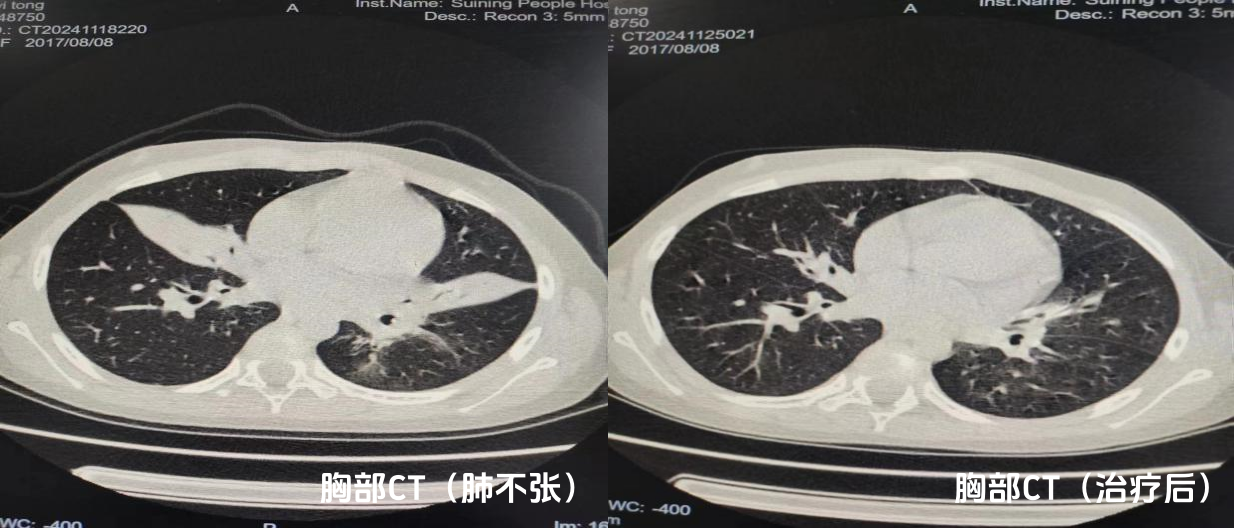

近日

在徐医附院专家的指导下

我院成功完成

数例儿童支气管镜肺泡灌洗治疗

为患儿“呼吸之路”保驾护航

该技术填补了

我县儿童纤维支气管镜检查的空白

标志着我院儿科诊疗技术取得了新的突破